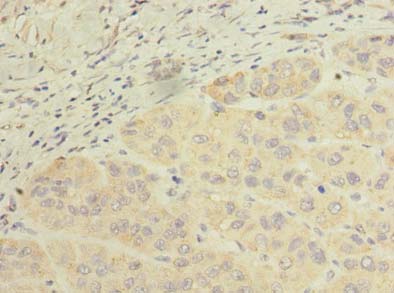

ApplicationELISA, IHC; Recommended dilution: IHC:1:20-1:200